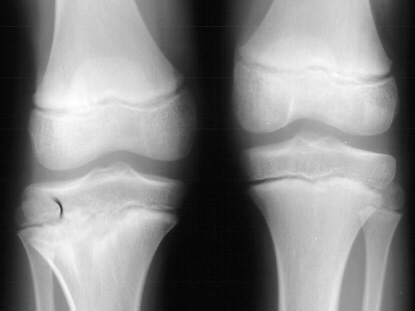

1 cm shortening of the right leg and a 10 degree valgus deformity

of the same knee(image 2). Radiological examination showed absence